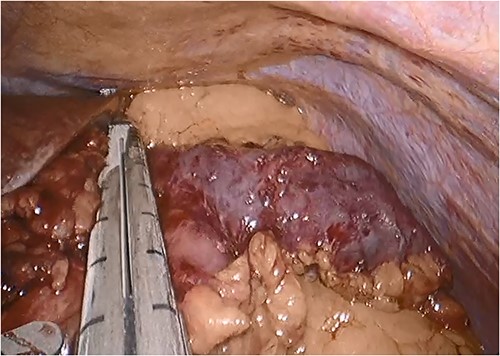

Since the patient’s symptoms persisted, she was referred to bariatric surgery. The patient was offered, and ultimately underwent, excision of the blind limb laparoscopically (seen in Fig. 4).

Intraoperative photograph showing the blind, afferent jejunal limb.